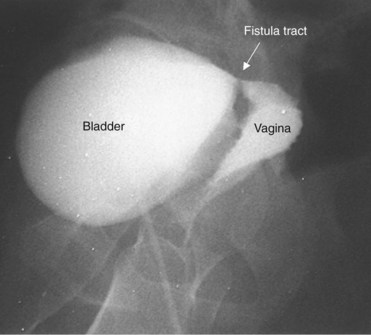

Vesicovaginal fistulae (VVF) are the most common acquired fistula of the urinary tract (Gerber and Schoenberg, 1993) and have been known since ancient times (Fig. 77–1). However, it was not until 1663 that Hendrik von Roonhuyse first described surgical repair of VVF by denuding the fistula margins and then reapproximating them with sharpened stiff swan quills (Margolis and Mercer, 1994). Johann Fatio is generally credited with the first successful VVF repair, in 1675, using von Roonhuyse’s technique (Falk and Tancer, 1954). In 1838, using leaden suture, John Peter Mettauer was the first U.S. surgeon to claim a successful VVF closure (Kight, 1967). In 1852, James Marion Sims published his now famous surgical series describing his method of surgical treatment of VVF using silver wire in a transvaginal approach (Sims, 1852). Of note, it was not until his 30th attempt at closure of VVF that he achieved success. However, Sims remains the subject of considerable debate regarding his ethics (Richardson, 1994; Sartin, 2004), because it is unknown whether the patients in his surgical series were willing and consenting participants (all were African-American slaves in pre–Civil War America). He was later to become one of the great figures in the history of operative gynecology. The first successful transabdominal approach to VVF repair was reported by Trendelenburg in 1888, and the concept of an interpositional flap was first proposed and reported in 1928 by Martius, who used a labial fat pad.

Figure 77–1 Voiding cystourethrogram demonstrates filling of the vagina with voiding due to a post-hysterectomy vesicovaginal fistula.

A cystogram and/or voiding cystourethrogram (VCUG) and an upper tract study should be performed in patients being evaluated for a VVF. The cystogram may objectively determine the presence and location of the fistula. Upon filling of the bladder, contrast often begins to opacify the vagina, almost immediately confirming the presence of a VVF. VVF are often best seen in the lateral projection (Fig. 77–7) in which the bladder and vagina are not superimposed. Often, the actual VVF tract may be visible in the lateral projection (Fig. 77–8). However, voiding images may be necessary in some patients with small fistulae, to demonstrate the VVF. The slight increase in intravesical pressure that accompanies micturition is usually adequate to demonstrate even very small fistulae. Importantly, a cystogram that fails to demonstrate a suspected VVF, but lacks voiding images or postvoid images, should be considered nondiagnostic. During voiding, care should be taken to exclude vaginal voiding or reflux of contrast from the introital region cephalad into the vagina, which would produce a falsely positive image. An involuntary bladder contraction can be provoked with rapid filling during cystography, and if the intravesical pressure rises sufficiently, this may also be sufficient to demonstrate a VVF when the filling images of the cystogram failed to demonstrate it. In some instances, a cystogram can also make an assessment of bladder capacity (important in the setting of prior radiotherapy), cystocele, bladder neck competence, and vesicoureteral reflux, any of which may have an impact on operative repair.